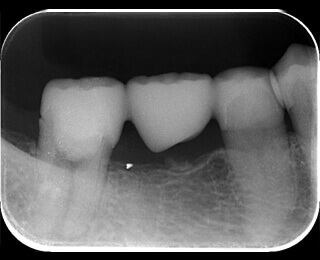

症例4 土台が大きくて治療できないようだ

15

太い金属(白く写っている部分)が入っており、その先の骨が溶けてます。

16

太い金属を安全に外し根の治療を終えました。骨は再生しています。